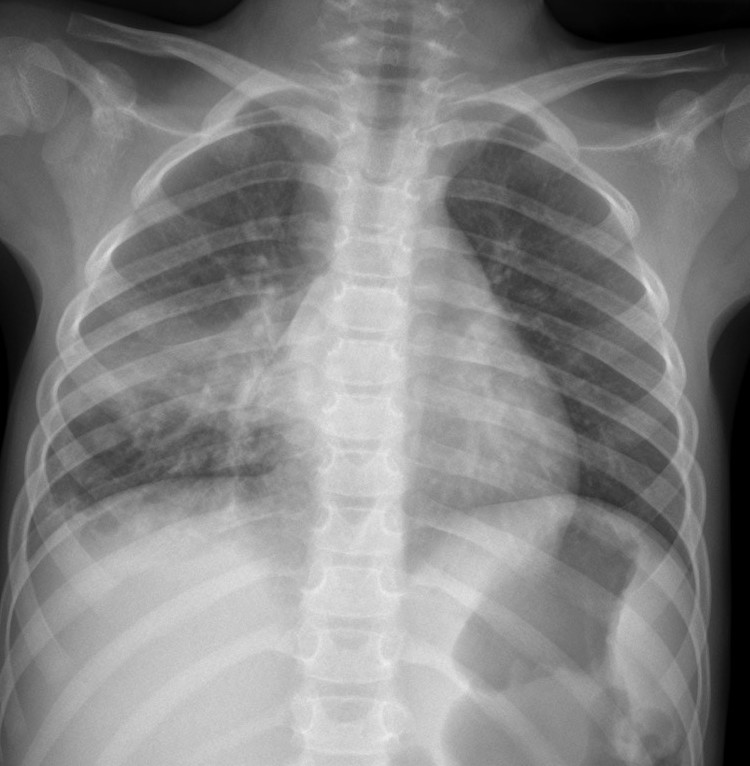

CASO: Dolor súbito en paciente asmático.

- Por la clínica presentada, debemos descartar un posible neumotórax. Sin embargo estamos ante una placa radiográfica con mala técnica.

- Se recomendó volver a realizar la radiografía, observar a continuación:

EXPOSICIÓN:

La penetración es la correcta cuando podemos visualizar la vértebras en su totalidad y las costillas a través del corazón.

El contraste es el adecuado si se pueden difrenciar adecuadamente estructuras con diferentes densidades: partes blandas, plumón y esqueleto.

La definición es buena si conseguimos que el paciente esté totlamente quieto durante la realización de la placa.